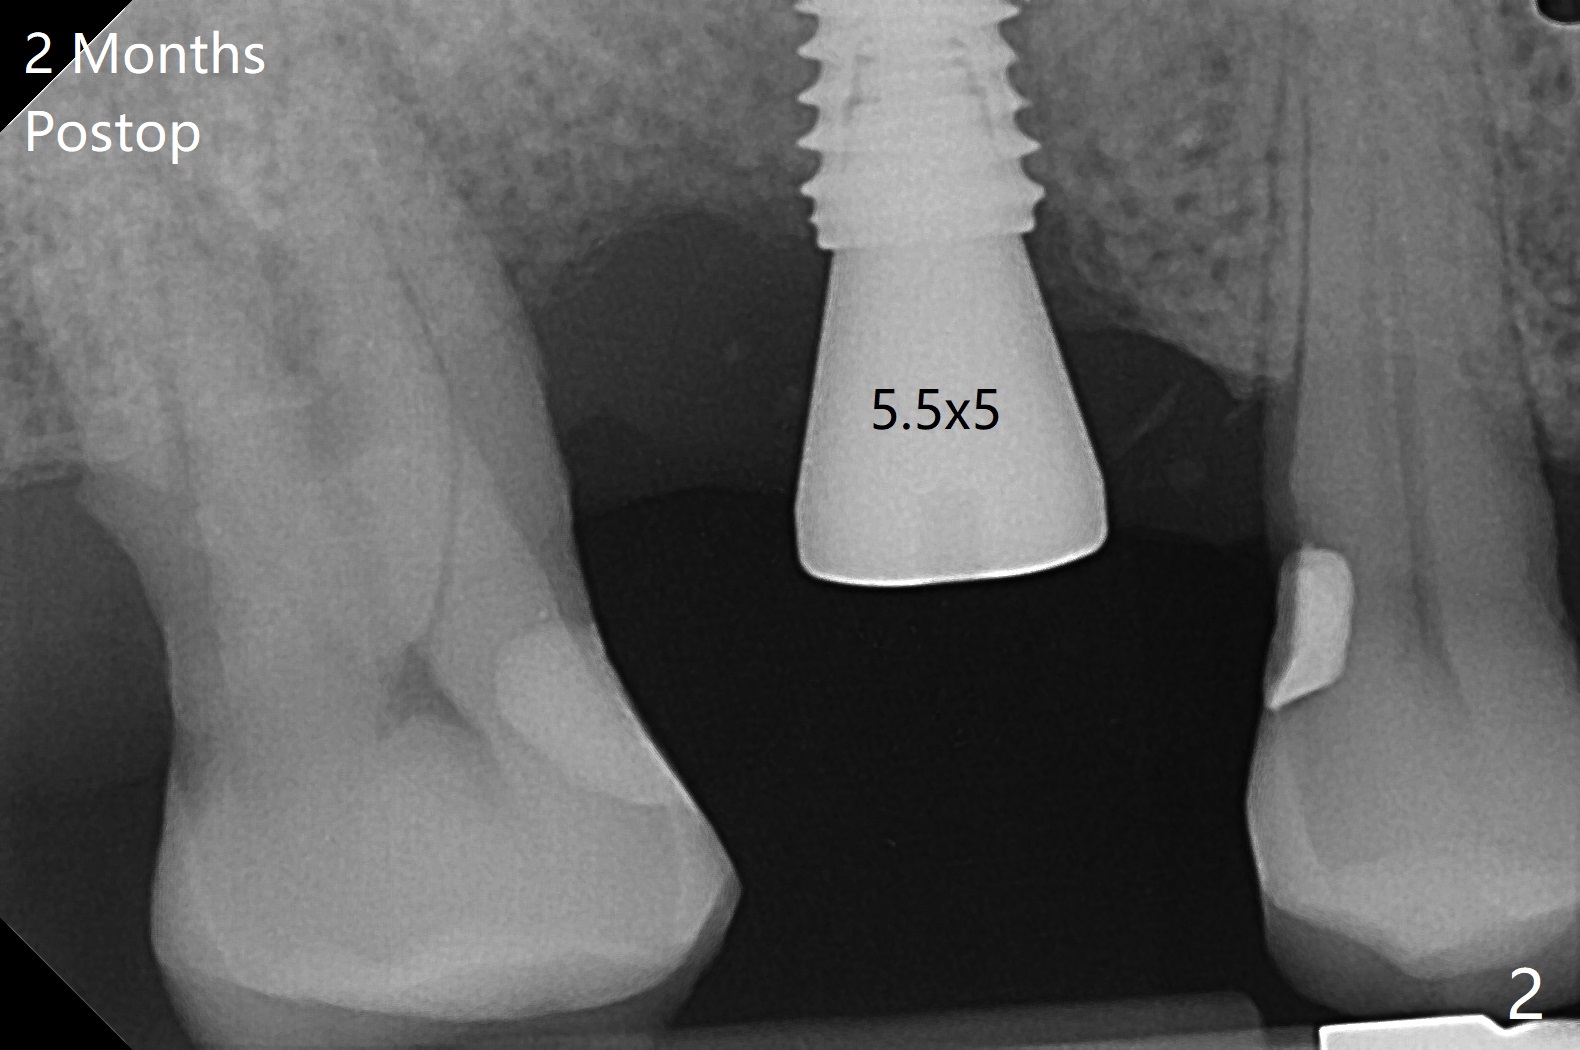

使用来自钻头的自体骨做提升,植体植入后,颊侧骨板薄,刚好骨下。使用5.5毫米profile drill后,放置愈合基台,术后三个月脱落,他再次要求修复,甚至提出退款,不愿意回诊所,因为他有糖尿病,新冠病毒高危人群。 放置小号愈合基台(图二)。他原来托牙是Valplast,没有occlusal rests,不能经过修改临时使用,可能将直接放置修复基台做临时牙冠。放置修复基台后(图三(术后三个月)),制作临时牙冠时,发现前者有些松动,后者就没有粘固。当基台完全就位,它最冠方与植体没有间隙(箭头),根方有间隙(空心箭头)。其实愈合基台也是一样(图一,二)。后来植体松动(术后4个月),拔除,植骨(图四),颊侧骨板缺失(图五:B)。植骨后5个月2号牙疼痛需要拔除种植(图七),与3号牙一起种植(图六),颊侧骨板修复,但是高度有所下降(箭头)。The narrow ridge with the intact buccal plate (Fig.8 >) can hold a 4x8.5 mm implant. The buccal plate is lost 4 months postop (Fig.9) and restores 5 months post graft (Fig.10). Return to Upper Molar Immediate Implant, No Deviation Coronal and Apical Gap in IBS implant Protect Graft Xin Wei, DDS, PhD, MS 1st edition 06/22/2020, last revision 05/02/2021